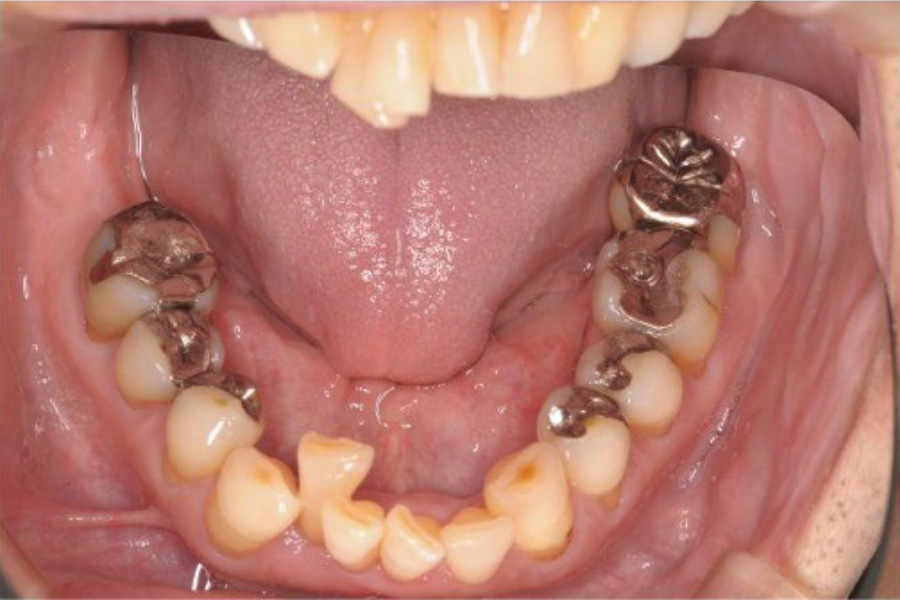

【50代男性】

数年前から左下の

一番奥の歯が噛んだときに痛む。

通院していた歯科で痛みはとれないがまだ抜かない方が良い

といわれたが、ずっと痛いままなので不安になり来院。

| 主訴 | 数年前から左下の一番奥の歯が噛んだときに痛む。 通院していた歯科で痛みはとれないがまだ抜かない方が良いといわれたが、ずっと痛いままなので不安になり来院。 |

| 治療内容 | 全顎治療:歯周病治療、抜歯、根管治療、 咬合治療・矯正治療、フルメタルクラウン(保険) |